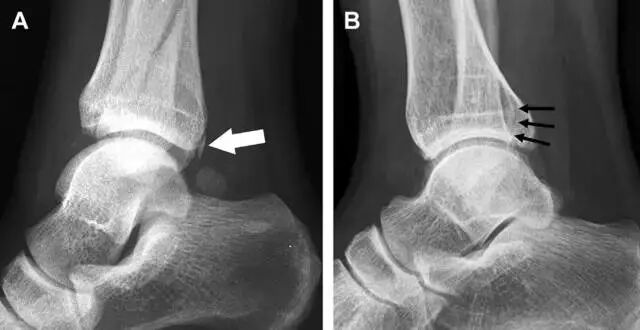

18距骨外侧突骨折

距骨外侧突骨折常因踝外翻背屈时,跟骨上外侧面撞击距骨外侧突下缘导致,或偶尔由踝内翻引起,被称为「滑雪板者骨折」。这种骨折只能在踝关节正位片上发现,而且外踝远端表面软组织肿胀往往是一个重要线索(图 4)。

图 4 距骨外侧突骨折。A 正位片示内翻损伤所致的距骨外侧突撕脱性骨折(箭头);B 另一位患者,踝外翻损伤导致典型的「滑雪板者骨折」,X 片上可见一较大的三角形骨折块(方框);C 第二位患者的 MRI 矢状位 T1 加权像示横行骨折(箭头)